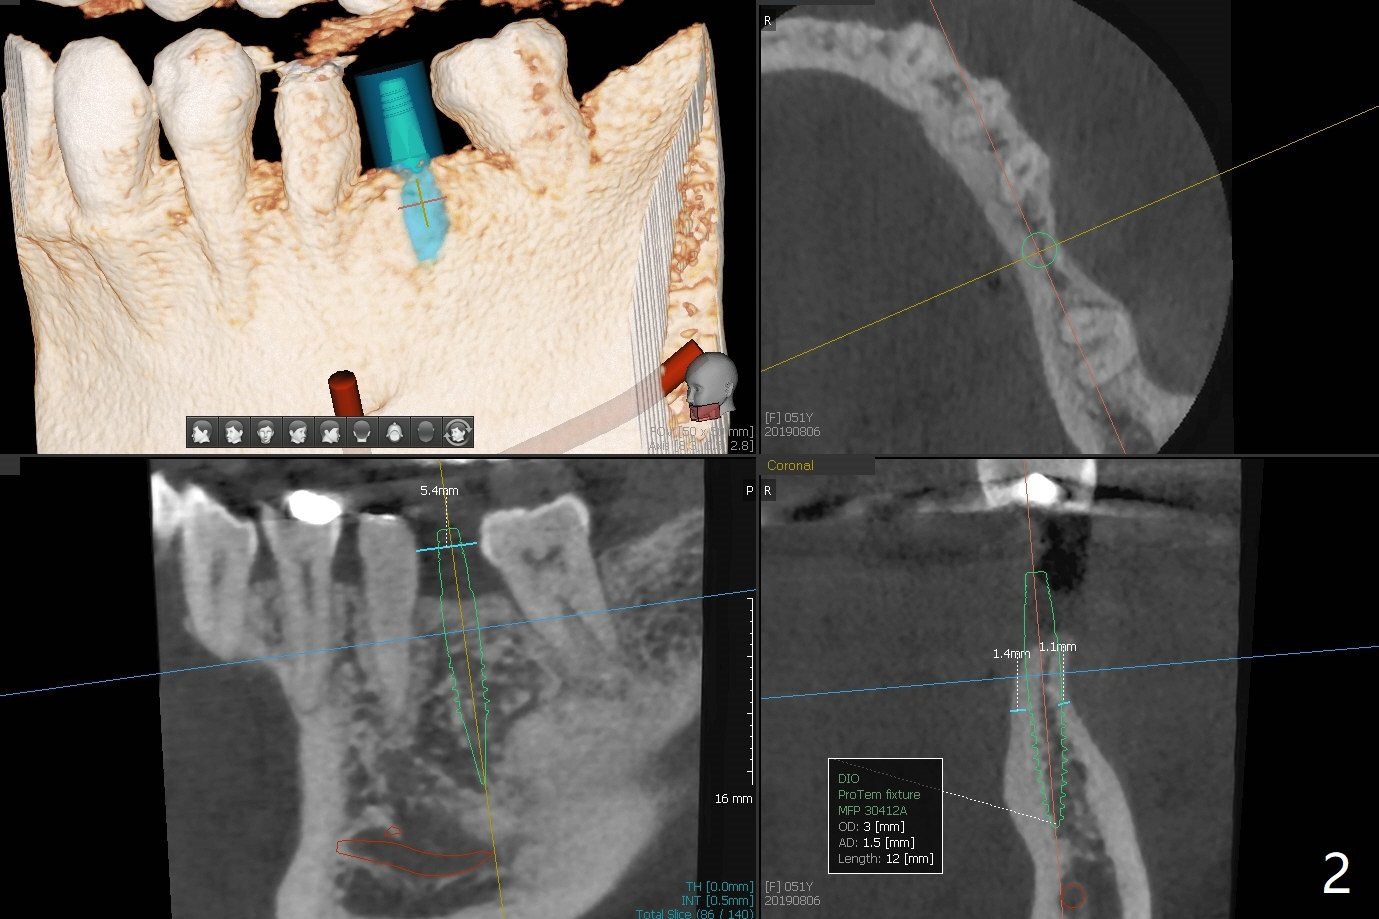

A 51-year-old woman has discomfort with #18-20 overcontoured FPD.  CT, taken after removal of the FPD, shows the narrow space and narrow ridge.  A 3.5 mm 2-piece (Fig.1) or 3.0 mm 1-piece (Fig.2,3) implant is indicated.  For ridge split, the ridge top will be trimmed with surgical handpiece and round bur (Fig.4).